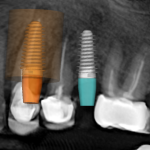

- The first stage: remove teeth No.23,24 + place 2 implant body

The first stage: remove teeth No.23,24 + place 2 implant body